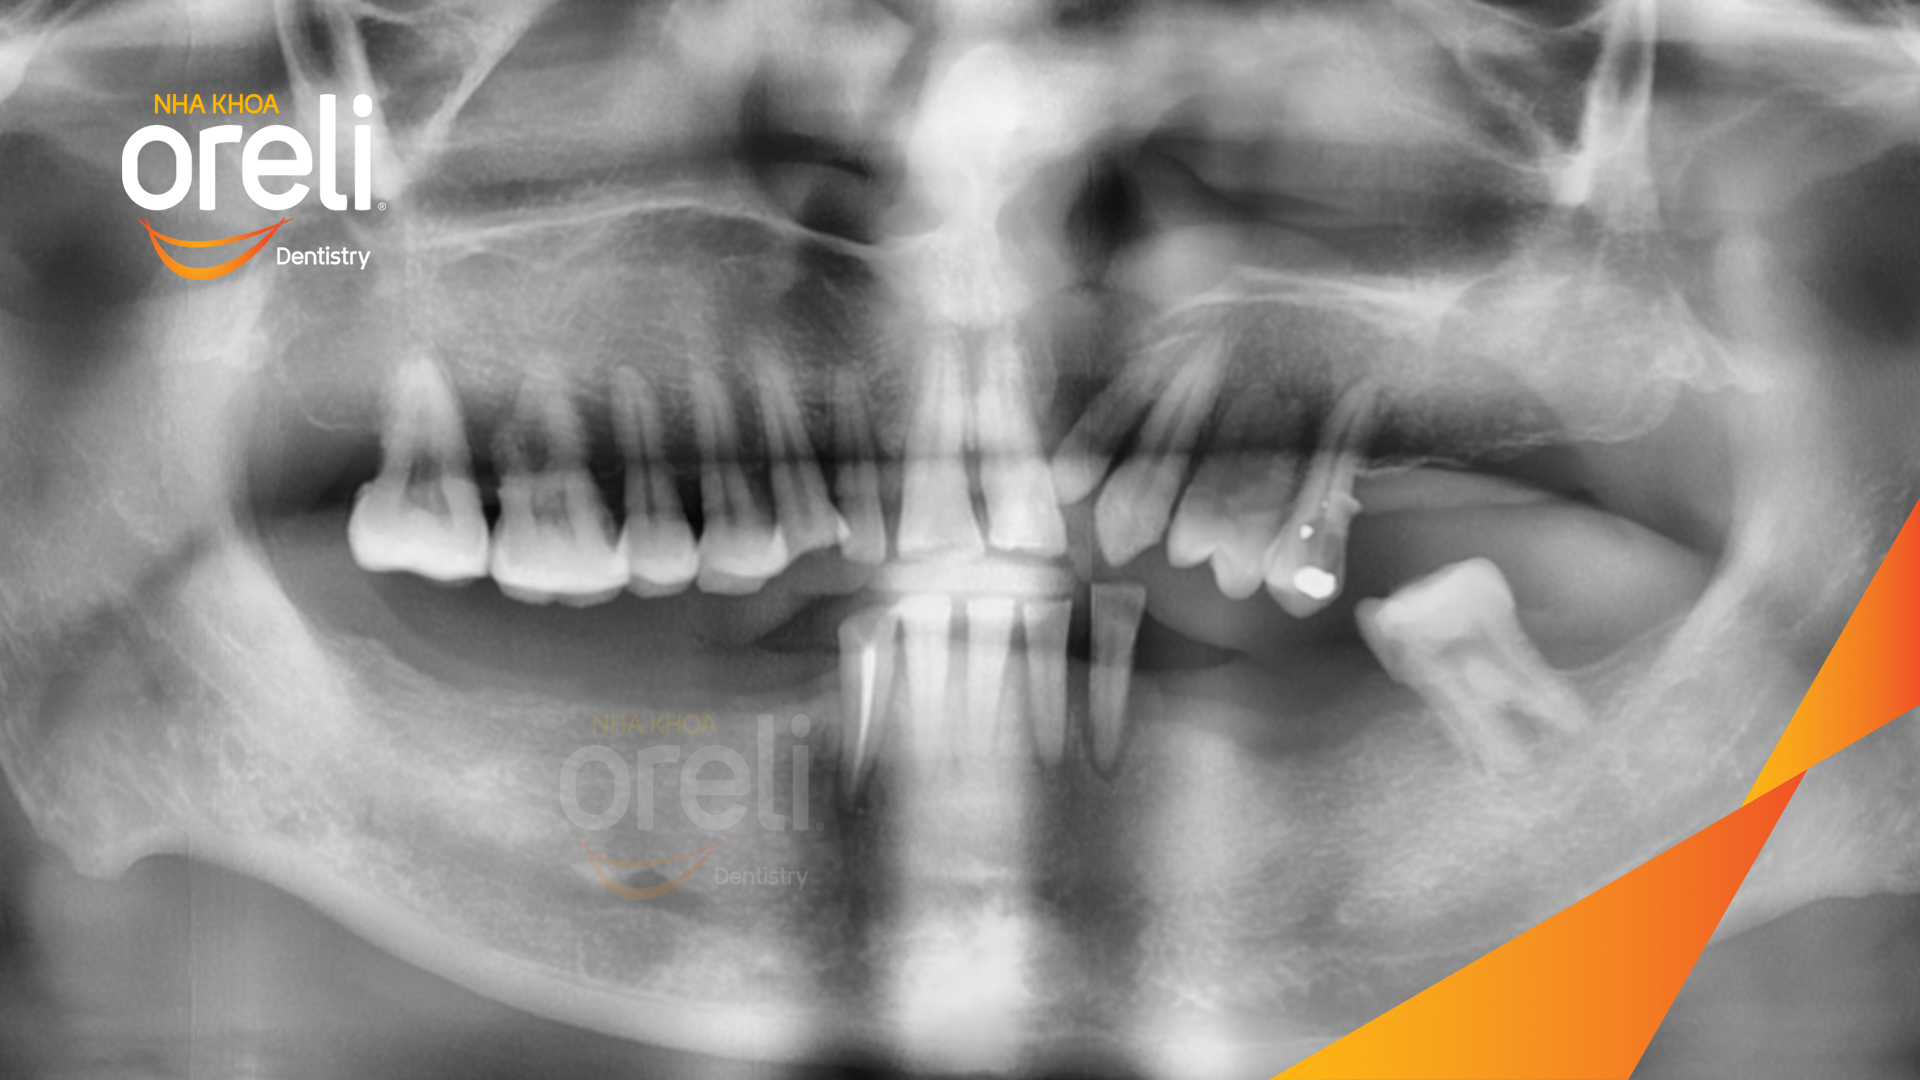

Tình trạng: Mất răng vùng răng sau hàm dưới, các răng trước lung lay mất khả năng hồi phục

Giải pháp: Nhổ răng trồng răng implant hàm dưới và hai răng hàm trên